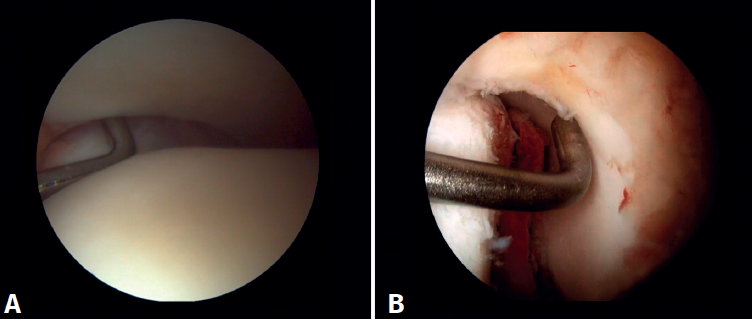

Arthroscopic evaluation of the syndesmosis

From the anteromedial portal we can directly visualize the distal fibers of the ATFL. Disinsertion of these fibers does not always result in instability of the syndesmosis, but it does require us to check it. In our experience, we prefer assessment of the coronal plane of the syndesmosis. We introduce the arthroscope into the tibiotalar joint directing the camera cranially. In this way we have a direct view of the distal tibiofibular joint. We then assess stability by attempting to insert the palpation probe into the joint. If it is possible to do so, we classify the syndesmosis injury as unstable (Figure 6A).

Arthroscopic evaluation of the deltoid ligament

There are multiple methods for assessing instability of the medial complex; using the anterior ankle portals it is possible to assess the stability of the deltoid ligament in its main plane of action, corresponding to the coronal plane. Chun et al.(20) described instability when it is possible to introduce an arthroscopic palpation probe into the medial tibiotalar space (Figure 6B). Vega et al.(21) reported that, in the majority of injuries, the most anterior portion of the deltoid ligament is detached from the medial malleolus, while its proximal insertions remain intact. In this situation, the arthroscopic palpation probe can be inserted between the medial wall of the internal malleolus and the deep fibers of the deltoid ligament.

Surgical technique: arthroscopic treatment of acute syndesmosis injuries

The technique should be performed using the conventional anteromedial and anterolateral portals. The anteromedial portal is used for visualization, while the anterolateral portal serves as the working portal. Once the tibiofibular space is visualized, the inflamed synovial component is resected with an arthroscopic shaver to facilitate reduction (Figure 7A). Then, under direct vision, we restore the tibiofibular space, carefully taking into account possible malrotation of the fibula, especially in Maisonneuve type fractures. For fibular reduction we use a Verbrugge clamp, which allows us to correct the rotation. In our experience, once the space has been cleaned and if the position is correct, it is infrequent to have to use a compression clamp between the tibia and fibula.

Surgical technique: arthroscopic treatment of acute medial complex injuries

In terms of surgical technique, the working portals are established in the same way as in conventional ankle arthroscopy: one anteromedial portal and one anterolateral portal. We always start with diagnostic arthroscopy to confirm the injury to the deltoid ligament. A probe can be used to verify the laxity of the fibers, and a test can be performed by inserting the probe through the medial groove: the lesion is confirmed if the instrument passes through. For repair, the viewing portal will be the anterolateral portal, thus allowing us to work more directly through the anteromedial portal. The anterior fibers of the superficial tibiotalar and intermediate fibers of the deep portion of the deltoid ligament are the ones that can be repaired with the arthroscopic technique(38). Once the ligament has been identified and dissected, a suture is passed between the fibers using a suture passer. The medial malleolus anchorage zone is prepared with a shaver or a small burr. With the ankle in neutral position, the anchor is inserted while maintaining the tension of the sutures. The intersection of the line parallel to the tibiotalar joint and a perpendicular line marked from the tip of the malleolus and along the lateral border of the malleolus can be used as an anatomical reference for placement(21). After reduction, we again test the fibers for tension and passage of the probe through the medial groove, to confirm adequate repair (Figure 8).